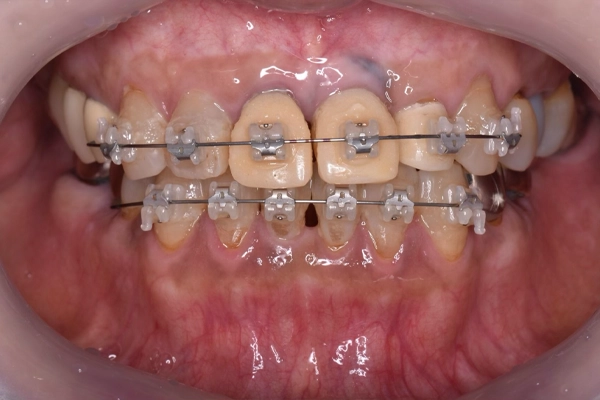

噛み合わせの状態

before

after

前歯の矯正治療

上顎と下顎の前歯の叢生(ガタガタした歯並び)の改善、左上2番の歯列改善のため右上3番〜左上3番、右下3番〜左下3番に唇側ブラケットを装着し歯列改善を行いました。

上顎はインプラントをアンカー(支点)として唇側傾斜、移動させ、下顎は右下1、2番と左下1、2番を中間地点くらいに移動させました。

矯正治療の様子

動的期間は6ヶ月、保定期間も6ヶ月設け最終補綴に向けた仮歯を作製し、装着しました。